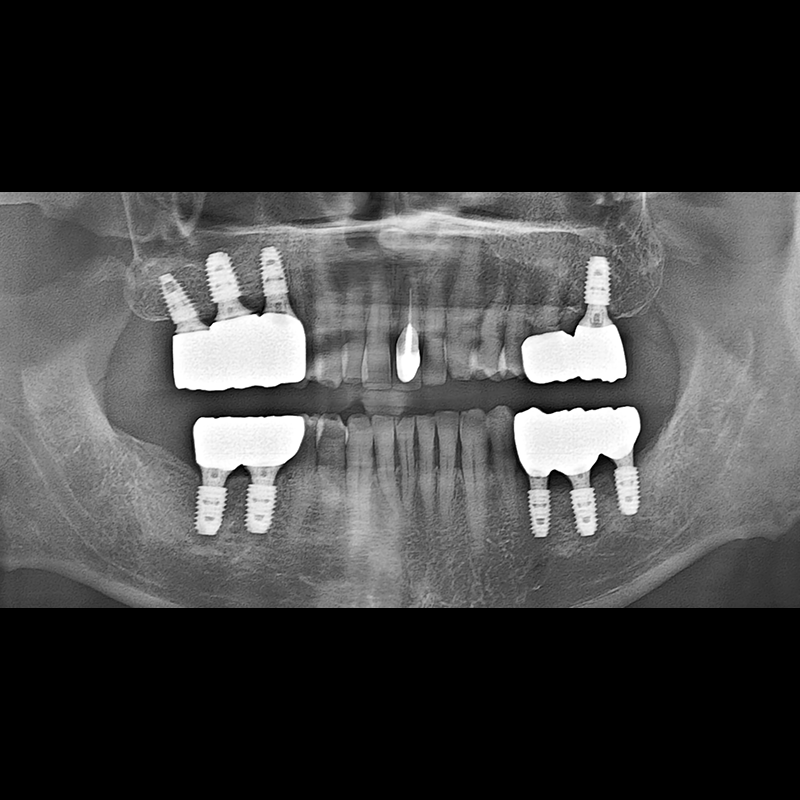

BEFORE AFTER

임플란트 전후사진 2025.05.30

결손된 치아 부분과 살리기 힘든 치아 위치에 임플란트를 식립하였습니다.